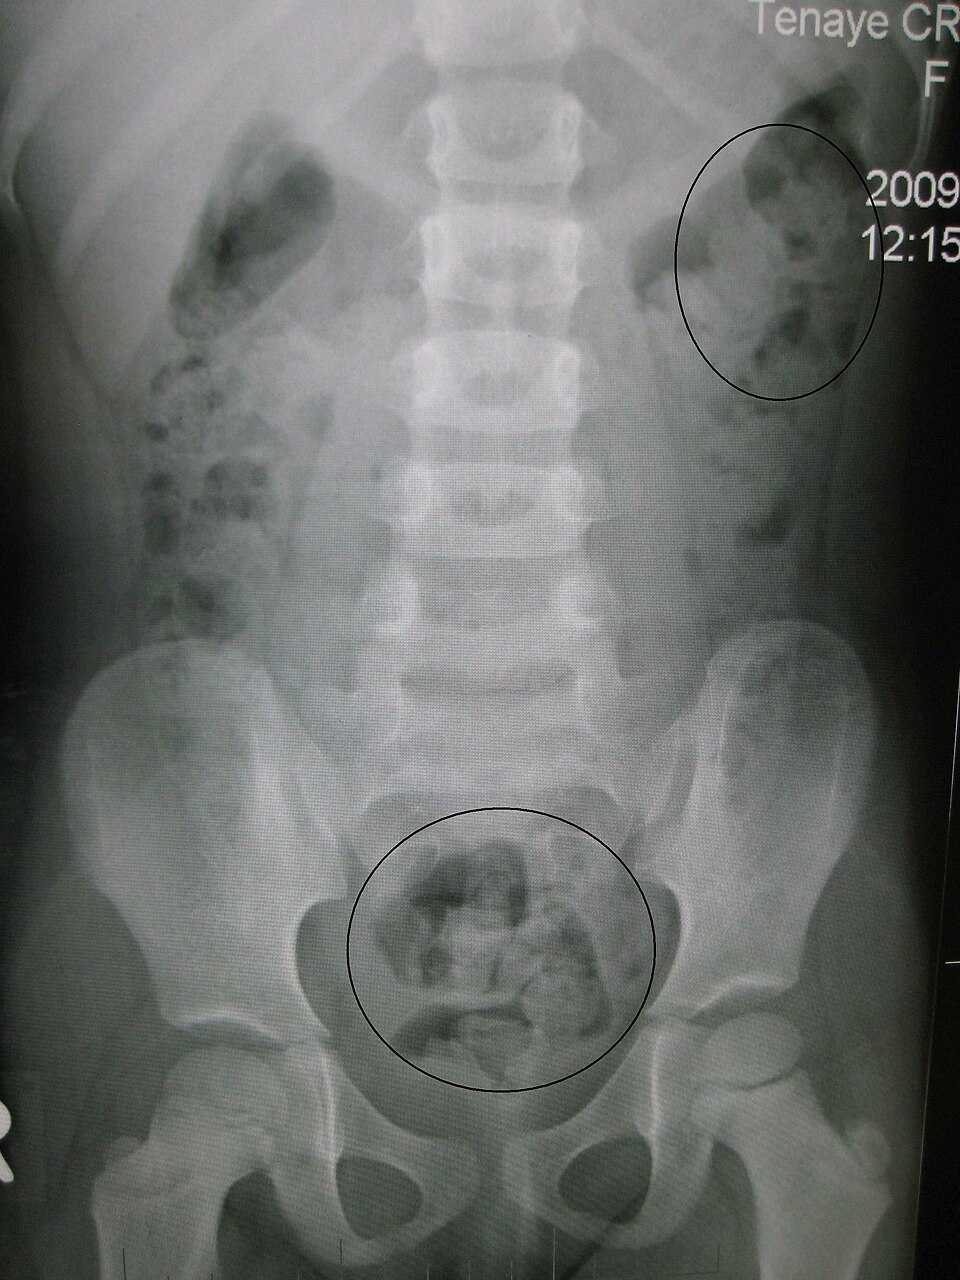

- 身長158cm、体重47.6kg

腸内に詰まったうんこの量6.7kg

肛門付近のうんこは水分は無くコンクリートのように硬化

妊婦のように腹が膨れてた(おならが溜まっていた)

腸内一部壊死

腸が破れなかったのは奇跡

- 死因は腸管内腔に,硬便を含めて大量(6.7kg)の便が,

異物として閉塞した単純性イレウス(機械的イレウス)による死亡であることがわかった。 - 62 名前:ここからは表現の自由でイカせていただきます 投稿日時:2025/11/23(日) 13:55:30.87 ID:aYQ2qBQH0